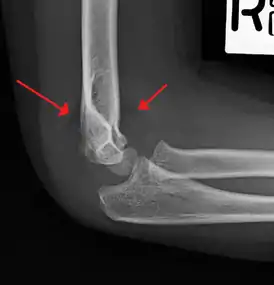

| An elbow X-ray showing a displaced supracondylar fracture in a young child | |

A supracondylar humerus fracture is a fracture of the distal humerus just above the elbow joint. The fracture is usually transverse or oblique and above the medial and lateral condyles and epicondyles. This fracture pattern is relatively rare in adults, but is the most common type of elbow fracture in children.[1] In children, many of these fractures are non-displaced and can be treated with casting. Some are angulated or displaced and are best treated with surgery. In children, most of these fractures can be treated effectively with expectation for full recovery.[2] Some of these injuries can be complicated by poor healing or by associated blood vessel or nerve injuries with serious complications.